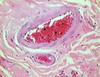

what is pictured

a Volkmann canal in compact bone extending from a Haversian canal